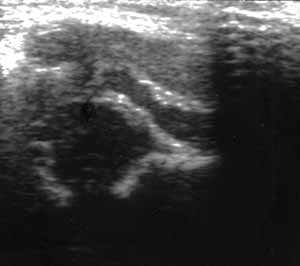

Ультразвуковая диагностика дисплазии тазобедренных суставов.

Рис. 5. Ультразвуковое изображение (Слева) и схема (Справа) нормального тазобедренного сустава со сглаженным костным выступом.